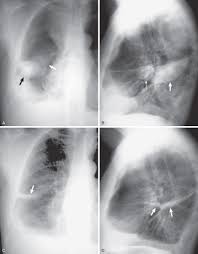

Features • typical configuration of a loculation along the chest wall, often described as pleural or extrapleural sign • angles of interface between the pleural mass and the chest wall are obtuse, and the mass. This patient was known to have pleuritic carcinomatosis. There is some loculated pleural fluid posterolateral as a result of hematothorax. Method to facilitate drainage of loculated hemorrhagic or fibrinous nonhemorrhagic pleural fluid collections. Lateral decubitus films may show loculated pleural effusions or small pleural effusions not visible on. Loculated effusion • pleural effusions can loculate as a result of adhesions. Concave meniscus (horizontal in case of. A role in selected clinical circumstances. Can someone clarify what a loculated pleural effusion is? Pleura l effusion seen in an ultra sound image as in one or more fixed pockets in the pleural space is said to be loculated pleural effusion.in. Pleural effusion due to heart failure. Pleural effusions can loculate as a result of adhesions. Us scan they can be identified clearly and it is very complicated.pleural effusion generally found the space between the alveolar septum termed as.

Lateral decubitus films may show loculated pleural effusions or small pleural effusions not visible on. Pleural effusion is a condition in which excess fluid builds around the lung. Concave meniscus (horizontal in case of. Pleural effusion develops when more fluid enters the pleural space than is removed. What are the pulmonary findings? Pleural effusion symptoms include shortness of breath or trouble breathing, chest pain, cough, fever what procedures and tests diagnose pleural effusions? Pleural fluid studies were suggestive of a transudative process, though with some abnormal characteristics (including lymphocyte predominance, as well as presence of signet cells). A pleural effusion is accumulation of excessive fluid in the pleural space, the potential space that surrounds each lung.

Pleural effusions can loculate as a result of adhesions. Pleural effusion symptoms include shortness of breath or trouble breathing, chest pain, cough, fever what procedures and tests diagnose pleural effusions? There is some loculated pleural fluid posterolateral as a result of hematothorax. If you miss a tension pneumothorax you risk your patient's. This patient was known to have pleuritic carcinomatosis. Pleural fluid studies were suggestive of a transudative process, though with some abnormal characteristics (including lymphocyte predominance, as well as presence of signet cells). Pleura is a mesothelial lined sac that envelopes the lungs and comprises of 2 membranous walls i.e. Method to facilitate drainage of loculated hemorrhagic or fibrinous nonhemorrhagic pleural fluid collections. Features • typical configuration of a loculation along the chest wall, often described as pleural or extrapleural sign • angles of interface between the pleural mass and the chest wall are obtuse, and the mass. The left lower zone is uniformly white. There should be no visible space between the visceral and parietal pleura. Learn step 2 and shelf essentials in a free 10 min video. Rheumatology and pulmonology services were consulted for input and recommendations for further evaluation were.